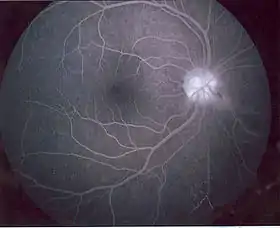

In the retina, the syndrome causes retinocephalic vascular malformations that tend to be present with intracranial hemorrhage and lead to decreased visual acuity, proptosis, pupillary defects, optic atrophy, congestion of bulbar conjunctiva, and visual field defects.[4][5] Retinal lesions can be unilateral and tortuous, and symptoms begin to appear in the second and third decades of life.[4]

There have only been 52 reported cases of patients with Bonnet–Dechaume–Blanc syndrome as of 2012.[2] Symptoms are rarely noticed in children and the syndrome is often diagnosed in late childhood or early adulthood when visual impairment is noticed.[3] Fluorescein angiography is commonly used to diagnose the syndrome.[6]

The ophthalmic features of Bonnet–Dechaume–Blanc syndrome occur as retinal arteriovenous malformation (AVMs). There are three categories of AVMs based on their severity. The first category consists of the patient having small lesions that usually are asymptomatic. The second category, more severe than the first, is when the patient's malformation is missing a connecting capillary between an artery and a vein; without it, edema, hemorrhage, and visual impairment can result. Category three refers to malformations so severe that their dilated vessels no longer distinguish between artery and vein, and the patient has a significantly increased risk of vision loss.[3] Since the retinal lesions categorized vary from large vascular malformations that affect a majority of the retina to malformations that are barely visible, the lesions can cause a wide range of symptoms, including decrease in visual sharpness, proptosis, pupillary defects, optic nerve degeneration, and visual field defects.[5] The most common type of visual field impairment due to AVMs is homonymous hemianopia,[2] which is usually unilateral.[7]

A number of examinations can be used to determine the extent of the syndrome and its severity. Fluorescein angiography is quite useful in diagnosing retinal features of the disease, and the use of ultrasonography and optical coherence tomography (OCT) are helpful in confirming the disease.[6] Neuro-ophthalmic examinations reveal pupillary defects (e.g. Marcus Gunn Pupil). Funduscopic examinations, examinations of the fundus of the eye, allow detection of arteriovenous malformations.[2] Neurological examination can determine neurological deficits such as hemiparesis and paresthesias.[2] MRI scans are used in imaging the brain and can allow visualization of the optic nerve and any possible atrophy. MRI, CT, and cerebral angiography may all be used to investigate the extent and location of any vascular lesions affecting the brain.[2][5]